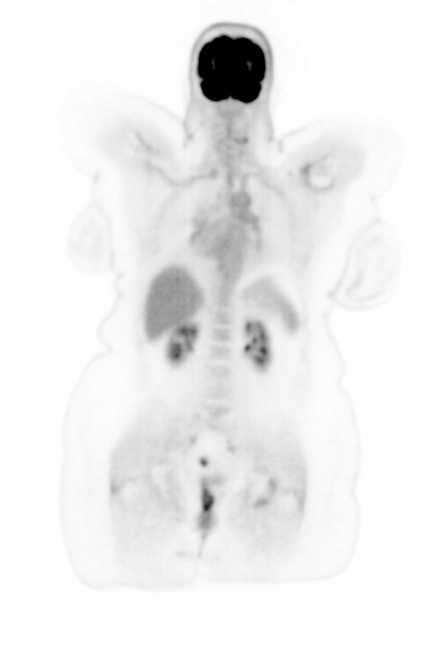

Figure 8 shows the correlation between activities in \acDLSE- and \acSSS-corrected \acPET images across different organs. Considering all \acpROI, the relationship between the mean activities of both methods is given by the regression function . Activity values are similar in the brain and lung regions, but \acDLSE-corrected images tend to show higher activity levels in the liver compared to \acSSS-corrected images.